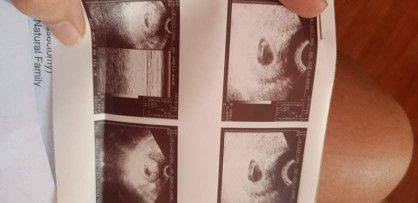

Normal lang po ba na may times na parang walang galaw si baby at minimal movements lang po ginagawa niya? 23 weeks now.

bAt your weeks yes po. Around 28 weeks importante na ang fetal movement monitoring